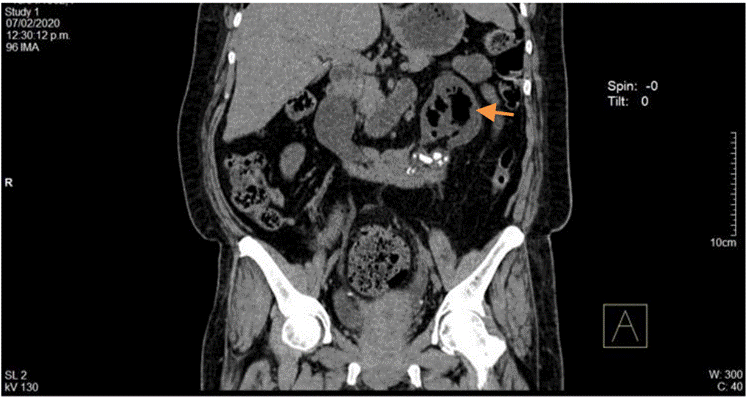

La paciente fue valorada por el servicio de medicina interna, el cual consideró hospitalizar con diagnóstico de infección de vías urinarias complicada sin respuesta a tratamiento antibiótico inicial, enfermedad diarreica aguda y enfermedad renal crónica agudizada, por lo que se inició manejo con fluidoterapia, cobertura antibiótica con piperacilina tazobactam, ajustado a función renal (TFG 20,2 mL/min/1,73 m2), y se solicitaron cultivos. Asimismo, se realizó ecografía con evidencia de riñón izquierdo aumentado de volumen, de contornos regulares, con presencia de ecogenicidades puntiformes en el grupo calicial superior con aspecto de gas. Se solicitó UROTAC (Figuras 5 y 6) que reportó gas en el sistema colector del riñón izquierdo, más específicamente en pelvis renal izquierda y dentro del uréter izquierdo, además de anomalía congénita de fusión renal (riñón en herradura), hidronefrosis leve izquierda con pelvis globulosa y múltiples litiasis a nivel de uréter distal y unión ureterovesical izquierda. La paciente tuvo expulsión espontánea de litos y descenso de azoados hasta niveles basales (1,9 mg/dL).

Dados los hallazgos compatibles con PNE Huang I (pielitis enfisematosa y ureteritis enfisematosa izquierda), se solicitó valoración por servicio de urología.